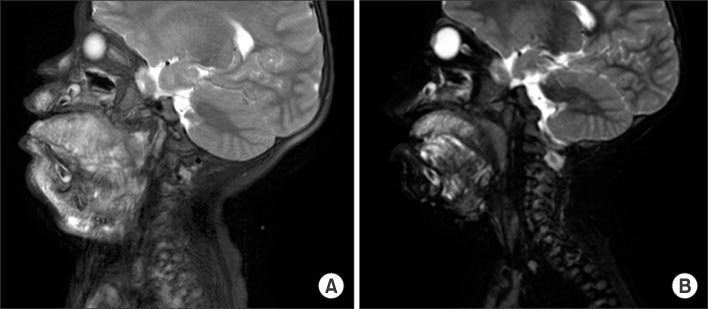

(A) Patient No. 2 was diagnosed with cervical lymphangioma prenatally by fetal MRI. (B) The patient was about to have a surgery 18 days after birth through EXIT procedure. (C) This picture was taken 1 year and 8 months after surgery. EXIT, ex utero intrapartum treatment.

Fig. 1 (A) Patient No. 2 was diagnosed with cervical lymphangioma prenatally by fetal MRI. (B) The patient was about to have a surgery 18 days after birth through EXIT procedure. (C) This picture was taken 1 year and 8 months after surgery. EXIT, ex utero intrapartum treatment.